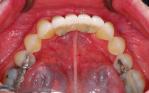

Replacement of all four failing lower front teeth with an implant bridge, some whitening, composite bondings and one new crown on an upper lateral incisor